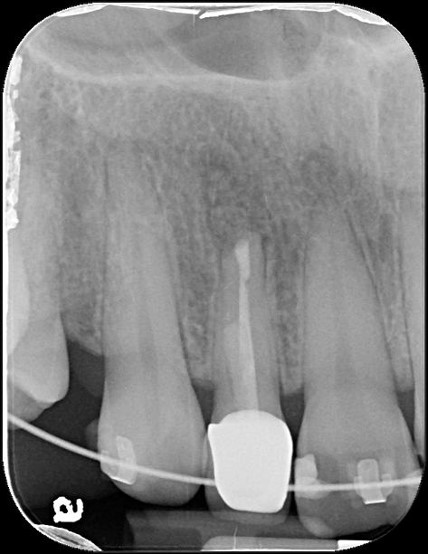

手術後根尖片